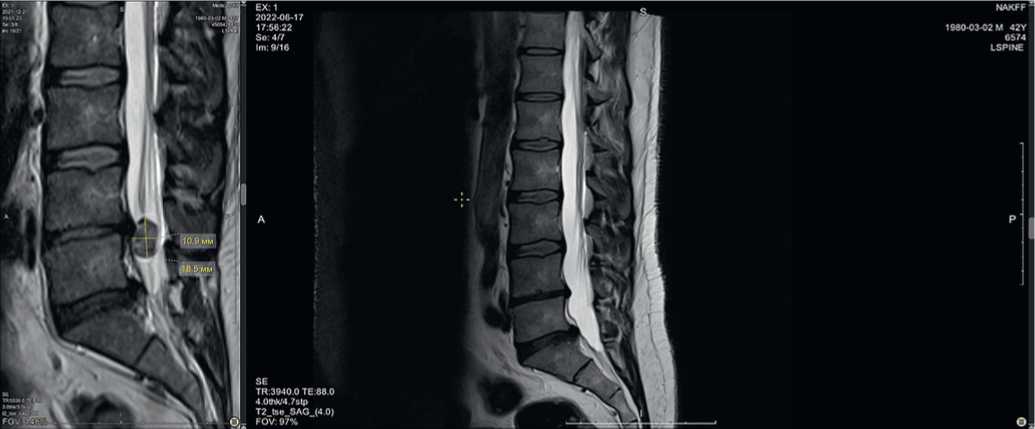

Пациент К., 41 года, обратился в Центр китайской медицины «Синь-я-Чжу» 22.12.2021 с жалобами на постоянную острую боль в пояснице с иррадиацией в правую нижнюю конечность, онемение пальцев стопы; движения ограничены — не может наклоняться, трудно сидеть. Ранее обращался к остеопатам и массажистам — без эффекта. Данные магнитно-резонансной томографии (МРТ) — грыжи дисков L4–L5, выступающая в спиномозговой канал на 13 мм, ширина секвестра 14 мм, каудальное распространение на 18 мм (рис. 2). Консультация нейрохирурга — рекомендовано оперативное лечение.

Рис. 2. Исходная магнитно-резонансная томограмма пациента К. при обращении 22.12.2021: A) саггитальный срез, B) аксиальный срез на уровне межпозвонкового диска L4-L5, C) фронтальный срез

Fig. 2. Initial magnetic resonance imaging of patient K. upon presentation on 22.12.2021: A) sagittal section, B) axial section at the level of the intervertebral disc L4-L5, C) frontal section

После лечения акупунктурой в течение 2 месяцев при контрольной МРТ от 07.03.2022 отмечена положительная динамика: уменьшение глубины грыжевого выпячивания до 7,5 мм, каудального распространения до 9,2 мм (рис. 3).

Рис. 3. Магнитно-резонансная томограмма пациента К. на фоне лечения 07.03.2022: A) саггитальный срез, B) аксиальный срез на уровне межпозвонкового диска L4-L5, C) фронтальный срез

Fig. 3. Magnetic resonance imaging of patient K. during treatment on 07.03.2022: A) sagittal section, B) axial section at the level of the intervertebral disc L4-L5, C) frontal section

На контрольной МРТ от 17.04.2022 определяется дальнейшее уменьшение глубины грыжевого выпячивания до 5,8 мм, распространение в позвоночном канале краниокаудально прежнее — 9,2 мм (рис. 4).

Рис. 4. Магнитно-резонансная томограмма пациента К. на фоне лечения 17.04.2022 г.: A) саггитальный срез, B) аксиальный срез на уровне межпозвонкового диска L4-L5, C) фронтальный срез

Рис. 4. Magnetic resonance imaging of patient K. during treatment on 17.04.2022: A) sagittal section, B) axial section at the level of the intervertebral disc L4-L5, C) frontal section

После курса акупунктуры при контрольной МРТ от 17.06.2022 отмечена выраженная положительная динамика: секвестр не определяется (обратное развитие), размеры грыжевого выпячивания значительно уменьшились (уменьшение глубины грыжевого выпячивания до 5,8 мм), признаки компрессии корешка не определяются (рис. 5).

Рис. 5. Магнитно-резонансная томограмма пациента К., саггитальный срез: A) исходная, B) после лечения 17.06.2022

Fig. 5. Magnetic resonance imaging of patient K., sagittal section: A) initial, B) after treatment 06.17.2022